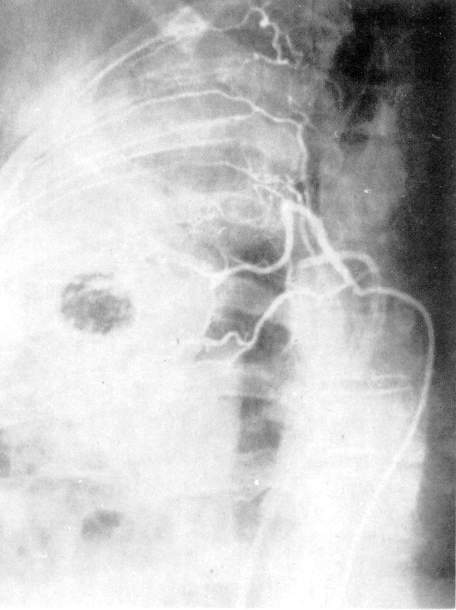

Рис. 7. Селективная ангиография бронхиальных артерий.

При селективной ангиографии бронхиальных артерий катетер вводится в грудную аорту и далее — до устья бронхиальных сосудов; введение контрастного вещества осуществляется с помощью автоматического инъектора. Сериография, проводимая, как правило, в переднезадней проекции, может быть дополнена рентгенограммами в боковой или косой проекциях в зависимости от задач исследования (рис. 7).

При анализе бронхиальных

ангиограмм определяются уровень и тип

анатомического ветвления сосудов,

положение, форма, диаметр, характер

контуров сосуда, извитость его и

проходимость, характер и уровень

окклюзии, степень развития коллатеральных

ветвлений и их взаимосвязь с легочной

артерией. Учитываются уровни

анастомозирования двух систем

кровообращения легких (субсегменты,

сегменты, доли или л

обулярные

ветви легочной артерии).